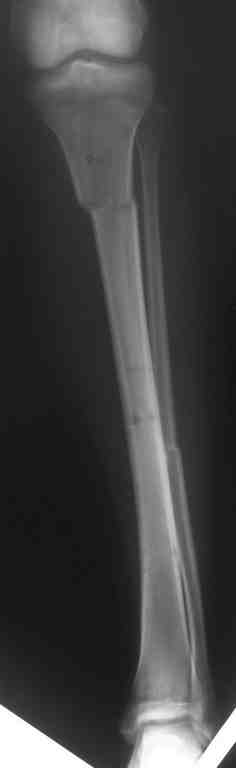

Выше представлены рентгенограммы открытого оскольчатого перелома нижней трети голени

X-rays of Compound Comminuted # Distal/3 Lt Tibia

Операционные снимки перед и после наложения аппарата Илизарова

In operation room before and after Ilizarov apparatus has been applied